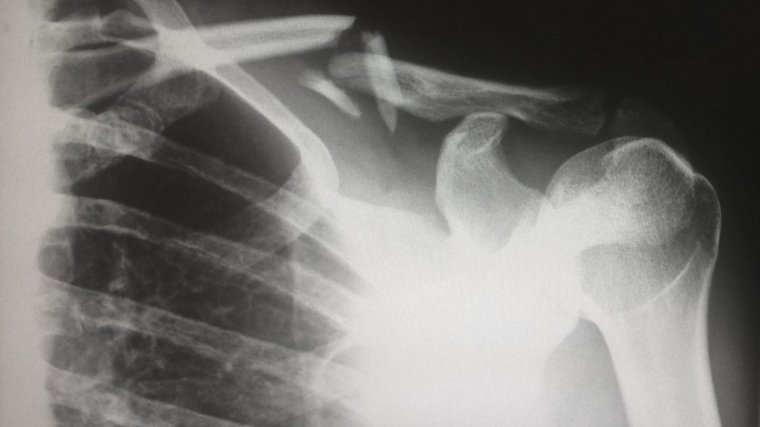

La osteoporosis es una enfermedad que provoca una disminución de la masa ósea y un deterioro general de los tejidos óseos. Ésto provoca una fragilidad en los huesos que, en consecuencia, también conduce a un aumento en el riesgo de sufrir fracturas.

Las zonas que suelen fracturarse más fácilmente debido a la osteoporosis son la cadera, la columna vertebral, la muñeca y las costillas. Aún así, la enfermedad puede afectar a cualquier hueso del cuerpo.

La proporción mineral de los huesos y la estructura ósea de un ser humano se encuentran en constante cambio, especialmente al inicio de la edad adulta. En este proceso, el tejido viejo se va descomponiendo y reabsorbiendo aproximadamente a la misma velocidad que se va creando tejido óseo nuevo.

A medida que una persona va envejeciendo, esta tasa de renovación va disminuyendo, cosa que hace que los huesos vayan quedándose más delgados y frágiles.